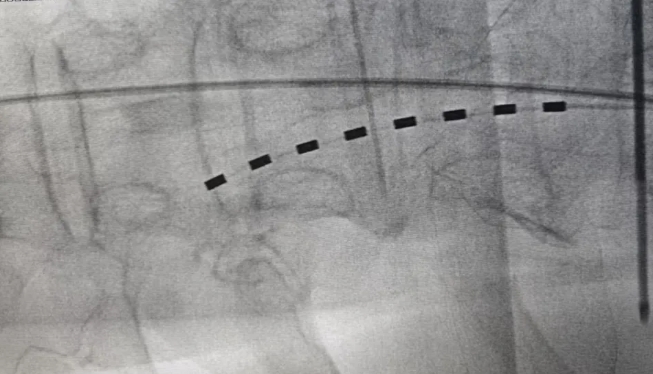

电极植入影像。

脊髓电刺激是一种微创手术,手术过程并不复杂。医生会在患者的背部开一个小切口,将一根细小的电极植入脊髓附近。电极通过一根导线连接到一个小型电池(通常植入在腹部或臀部皮下)。